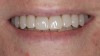

A patient wanted to change the shade, shape, and symmetry of her maxillary anterior teeth. Even after going through orthodontics to align the long axes of the anterior teeth, the patient wanted to "fine-tune" her smile by changing the overall shade and shape while eliminating the unsightly "dark triangles" present, especially between teeth Nos. 8, 9, and 10. Another concern was to preserve as much natural existing tooth structure as possible because there were no preoperative caries present on teeth Nos. 4 through 13. Conservative veneers were chosen to achieve her preoperative goals. The plan was to place pressable ZLS veneers from teeth No. 4 through No. 13 to take advantage of the chameleon effect of the natural teeth (Figure 1 through Figure 6).